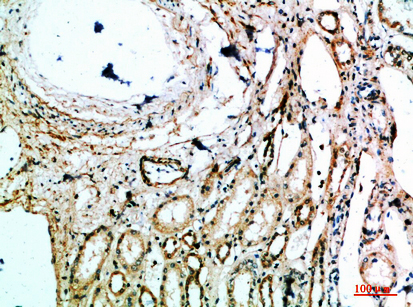

Immunohistochemical analysis of paraffin-embedded human-brain, antibody was diluted at 1:200

,

Immunohistochemical analysis of paraffin-embedded human-kidney, antibody was diluted at 1:200